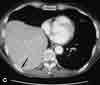

You order a CT scan to investigate these findings further.An axial image (C) demonstrates the dependent viscerasign, in which the liver makes contact with the posteriorribs (arrow); this strongly suggests a right-sided diaphragmatichernia.

You order an MRI study to confirm your suspicions.Coronal (D) and sagittal (E) T1-weighted images show arent in the center of the diaphragm (arrows) throughwhich the right lobe of the liver herniates. The CT andMRI images clearly point to increased intra-abdominal/intrapelvic pressure as the cause of both the pelvicfractures and the rupture of the diaphragm.